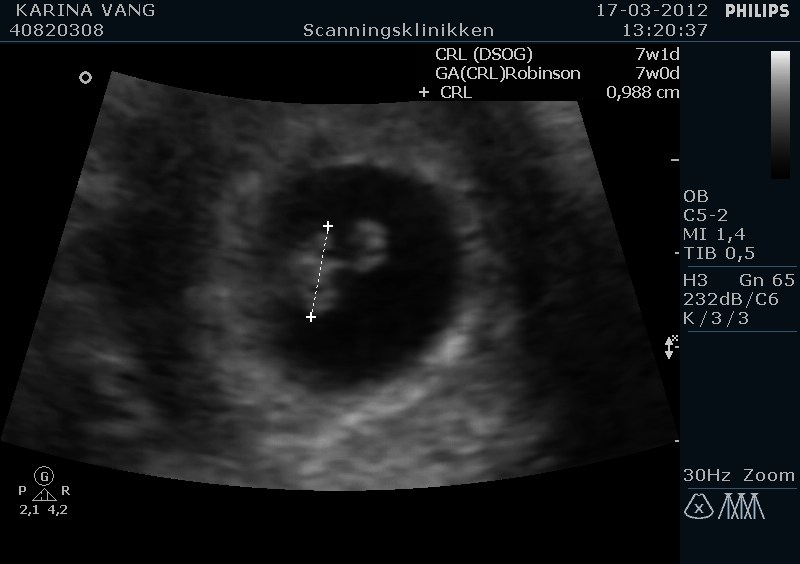

Som jeg skrev tidliger, så skulle vi til tryghedscanning i går i Århus og se vores bebs for første gang

Vi var begge rigtig nervøse for om det hele nu var som det skulle være, men det var DET  og vi er bare såååå glade !!! det er helt vildt

Det var den bedste oplevelse nogenside !! det var bare så stort at se den lille spire i ens mave og den havde det fineste lille hjerteblink